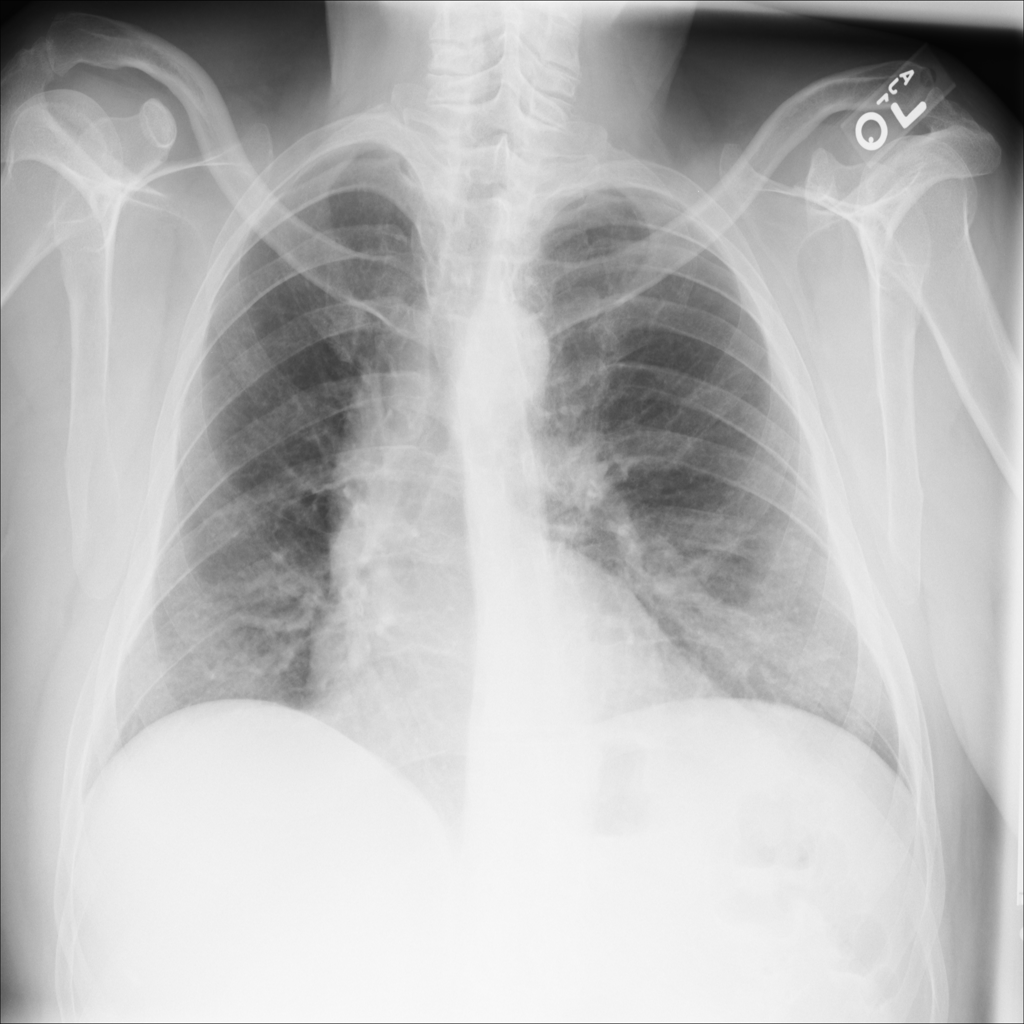

PAT-22A7 · IMG-003Emphysema

PAT-22A7 · IMG-003

PA